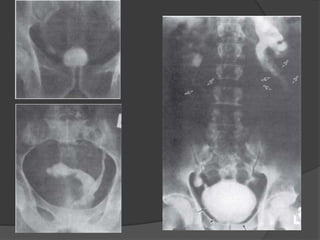

Rx

RAS: Áreas grises en fosa renal (Riñón

hidronefrotico hipertrofico) o área

vesical (tumor).

Opasificaciones (cálculos) riñón, uréter

o vejiga. Calcificación lineal en pared

ureteral y vesical.

Calcificación punteada del uréte4r

(ureteritis calcinosa), en panal de la

vesícula seminal.

UE (TC Abd y Pélvica): Función renal

normal o disminuida y grados de

dilatación de VUS (HS, Uréteres

dilatados, Estenosis ureteral o vejiga

contraída y pequeña con opacidad mL.

UR: Estenosis uretral

esquistosomatosa

Cistografías: RVU